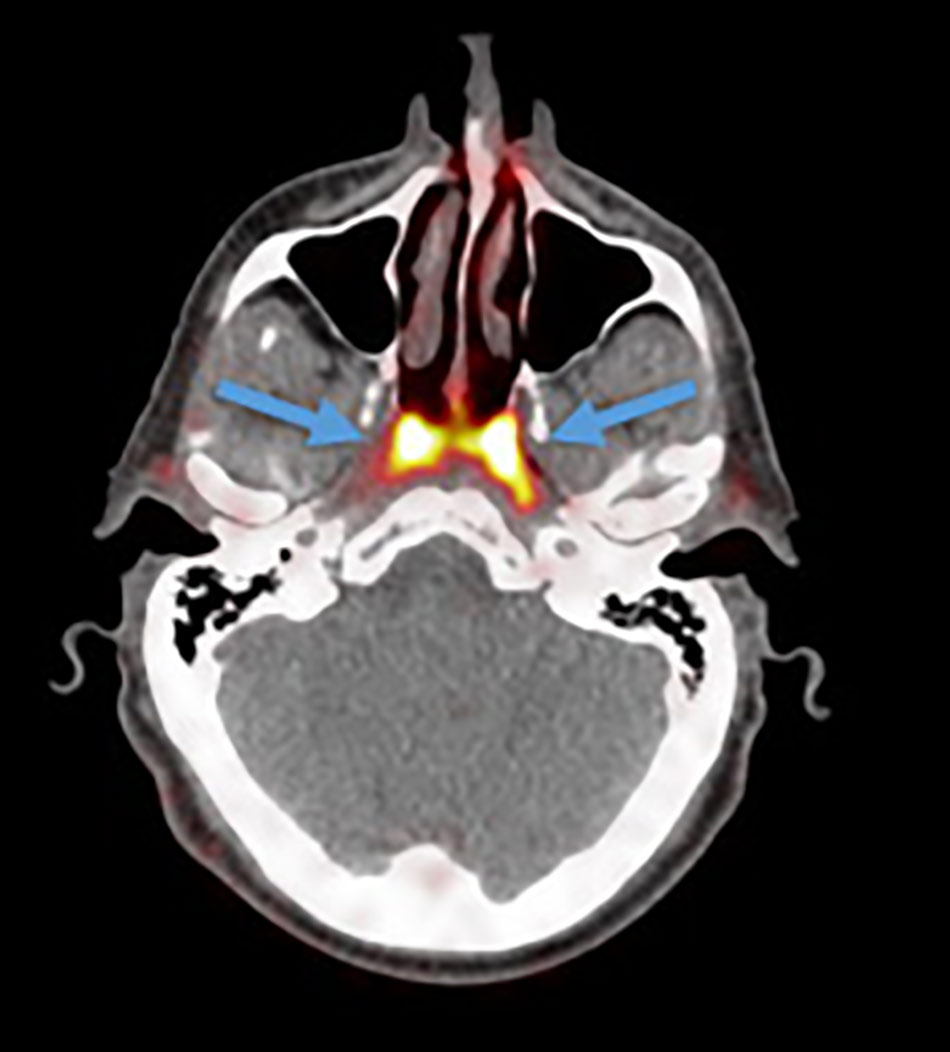

वैज्ञानिकों ने इंसानी शरीर में एक नए अंग का पता लगाया है. नीदरलैंड के वैज्ञानिक एक नए 'कैंसर स्कैन' की जांच कर रहे थे जब उन्हें गले में एक नए अंग का पता चला. रिसर्चर्स ने पाया कि इंसान के गले के ऊपरी हिस्से में ग्रन्थियों का एक ग्रुप है जिसके बारे में अब तक पता नहीं था.

वैज्ञानिकों ने शरीर में पता चले इस नए अंग को Tubarial salivary glands नाम दिया है. वैज्ञानिकों का मानना है कि यह अंग नाक के लूब्रिकेशन में मदद करता है.

नीदरलैंड के एम्सटर्डम के कैंसर इंस्टीट्यूट के वैज्ञानिक प्रोस्टेट कैंसर की जांच के लिए तैयार किए गए PSMA PET-CT नाम के स्कैन का परीक्षण कर रहे थे. इस दौरान डॉक्टर्स एक रेडियोएक्टिव ट्रेसर को मरीज के शरीर में इंजेक्ट करते हैं. रेडियोएक्टिव ट्रेसर की वजह से ही नए अंग का पता चला.

वैज्ञानिकों का कहना है कि ग्रन्थियों के जिस समूह का पता चला है कि वह 1.5 इंच लंबा हैं. यह salivary glands की तरह ही है. स्टडी के दौरान जिन 100 मरीजों की जांच की गई, सभी में यह अंग मौजूद था.